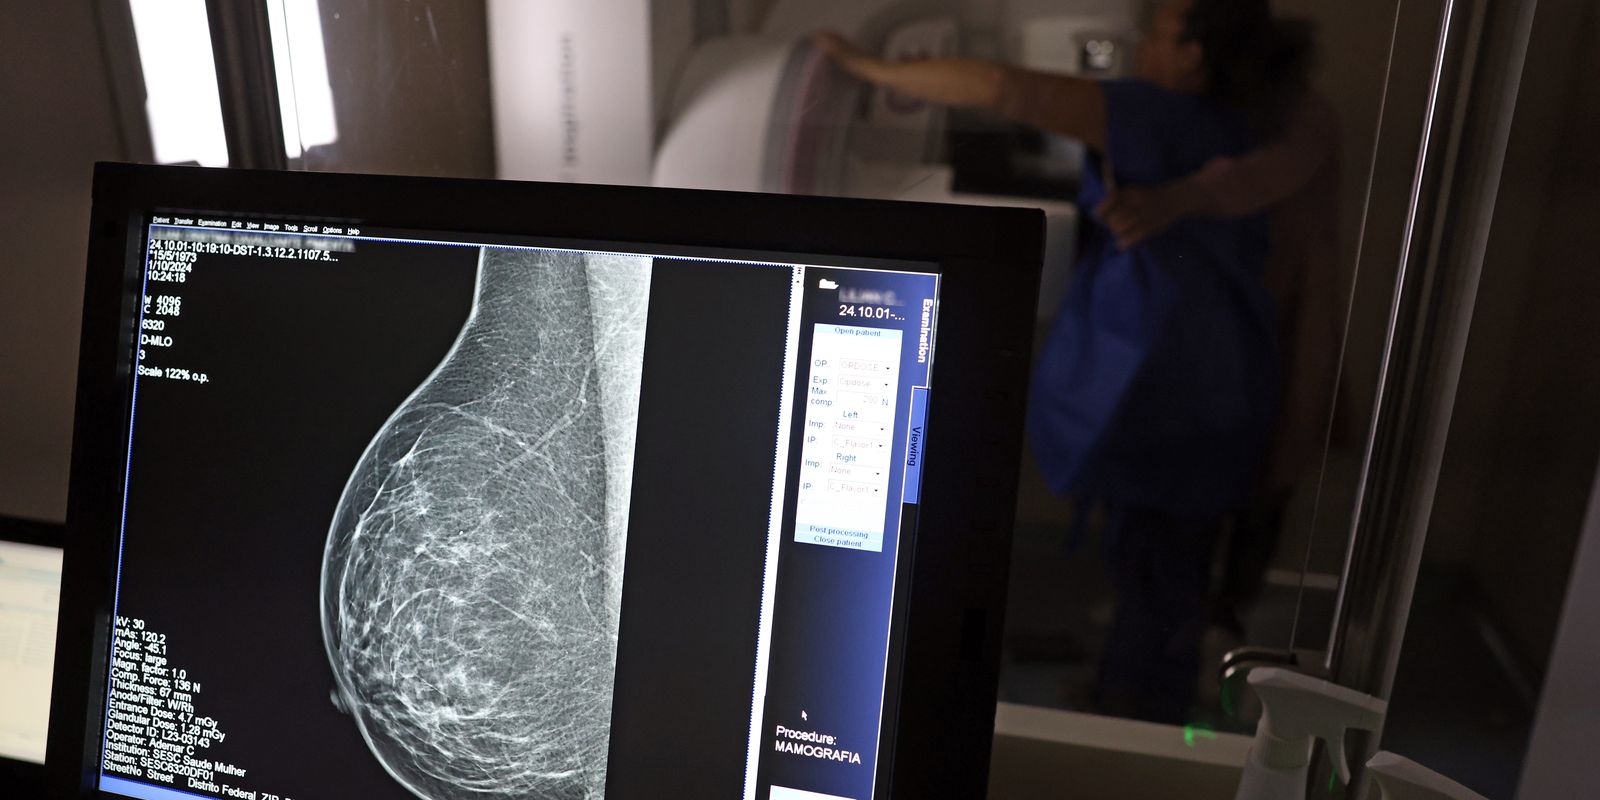

Uma nova lei, publicada nesta segunda-feira (6), reforça o direito do trabalhador com contrato via Consolidação das Leis do Trabalho (CLT) de se afastar até três dias por ano para realizar exames preventivos de câncer, em desconto salarial.

O direito já estava incluído na CLT desde 2018. A partir de agora, as empresas passam a ser obrigadas a divulgar essa informação, além de outras relacionadas a campanhas oficiais de vacinação contra o HPV e sobre o acesso a serviços de diagnósticos de cânceres de mama, próstata e de colo do útero.